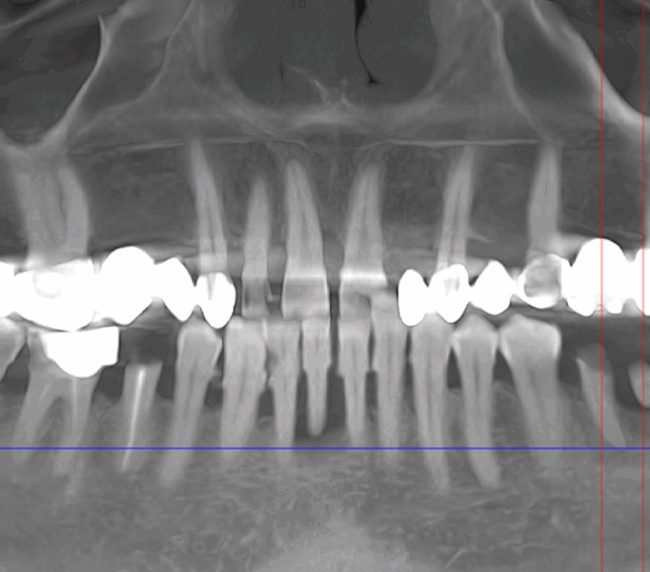

- Consultație, radiografie și plan de tratament personalizat

- Amprentă digitală cu scanner intraoral sau clasică

- Tehnologie CAD/CAM și scanare digitală 3D